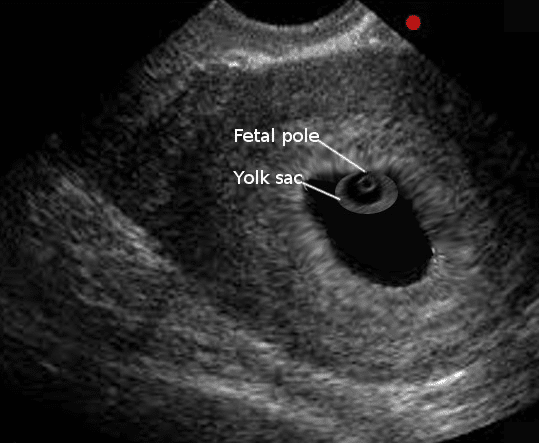

Marcos do primeiro trimestre

O saco vitelino é uma estrutura anatômica esférica, com centro sonolucente e periferia ecogênica. Ele pode ser observado nas primeiras semanas da gestação, geralmente quando o diâmetro médio do saco atinge aproximadamente 5 mm. No entanto, em alguns casos, pode não ser visível até que o diâmetro se aproxime de 8 mm.

Pontos-chave sobre a avaliação do saco vitelino por ultrassonografia transvaginal incluem:

- O saco vitelino torna-se visível pela primeira vez por volta da 5ª semana de gestação e normalmente se degrada entre as 10 e 12 semanas;

- O diâmetro do saco vitelino tem uma correlação pobre com a idade gestacional, portanto, não é utilizado para estimar a idade gestacional e DPP;

- Para confirmar uma gravidez inviável, nenhum saco vitelino ou pólo embrionário deve ser visível quando o diâmetro médio do saco atinge 25 mm.